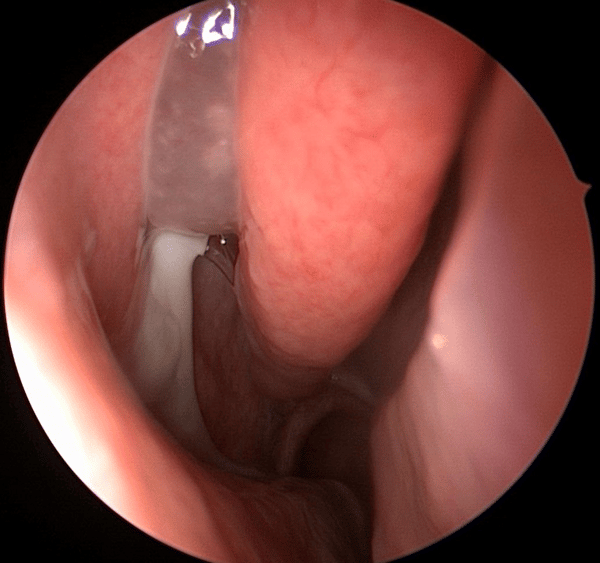

visão endoscópica Sinusite